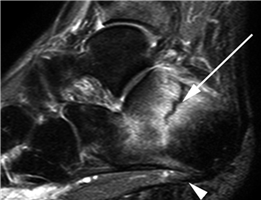

The first ray functions as an independent biomechanical column consisting of the medial cuneiform and the first metatarsal. The first TMT joint is a complex, kidney-shaped articulation that exhibits primary motion in the sagittal and coronal planes. Hypermobility at this joint is a highly debated topic, yet it remains a critical consideration in the surgical planning of Lapidus arthrodesis. The vascular supply to the first metatarsal head is tenuous, supplied primarily by the first dorsal metatarsal artery and the plantar medial and lateral arteries. The intraosseous blood supply enters the metatarsal neck and travels proximally; thus, aggressive lateral soft-tissue stripping combined with a distal osteotomy poses a well-documented risk of avascular necrosis (AVN).

The sesamoid complex, embedded within the flexor hallucis brevis (FHB) tendons, acts as a fulcrum to increase the mechanical advantage of the intrinsic flexors. The tibial (medial) and fibular (lateral) sesamoids articulate with the plantar facets of the first metatarsal head, separated by the crista. In severe hallux valgus, the metatarsal head pronates and drifts medially off the sesamoid apparatus, leading to erosion of the crista and intractable pain. Surgical realignment must restore this delicate sesamoid-metatarsal relationship to ensure long-term success and prevent recurrence.

Weight-bearing anteroposterior (AP), lateral, and sesamoid axial radiographs are mandatory. On the AP view, the surgeon measures the Hallux Valgus Angle (HVA, normal < 15°), the Intermetatarsal Angle (IMA, normal < 9°), and the Distal Metatarsal Articular Angle (DMAA). The lateral view is scrutinized for Meary's angle (talo-first metatarsal angle) to identify midfoot collapse, as well as the presence of dorsal osteophytes indicative of hallux rigidus. The sesamoid axial view is critical for assessing the degree of sesamoid subluxation and the integrity of the crista.